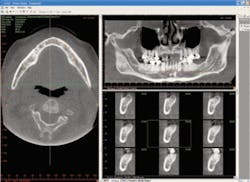

Cone beam

Cone beam or 3-D imaging is the new frontier for digital radiography. While these systems go by many different names, the best way to describe the system is that it’s a cross between a digital pan/ceph and a CAT scan machine. The most popular model right now in the United States is the i-Cat by Imaging Sciences. While I could describe the system in detail, this excerpt from an i-Cat user does the best job of explaining why they are becoming so popular: “Compared to medical scanners, cone beam scanning is 10 times more accurate while reducing a patient’s exposure to radiation by more than 95 percent. Pre-surgical implant treatment planning, preparing to remove impacted third molars, determining how sinus grafts and ridge augmentations have healed, and determining the ideal position for single-tooth replacements are just some of the benefits of cone beam scanning technology. Since cone beam scanning permits multiple slices through the axial, sagittal and coronal views, it removes the guesswork in many situations, such as when it is critical to determine the width of edentulous ridges, whether or not cancellous bone exists between cortical plates, the position of supernumerary and developing tooth buds, whether sockets have filled with bones, if irregularities exist to the condyles, where the mandibular nerve is relative to an impacted tooth and implant sites, or to visualize the borders of a cyst or tumor. Cone beam scanning has an added benefit of being able to take the maxilla and mandible in a single scan.”

Probably the biggest drawback to these systems is the initial cost: around $170,000 to $200,000 each. Dentists all over the country are grouping together to create imaging centers and share the costs of the machines. The cone beam may eventually be the standard of care for many procedures.